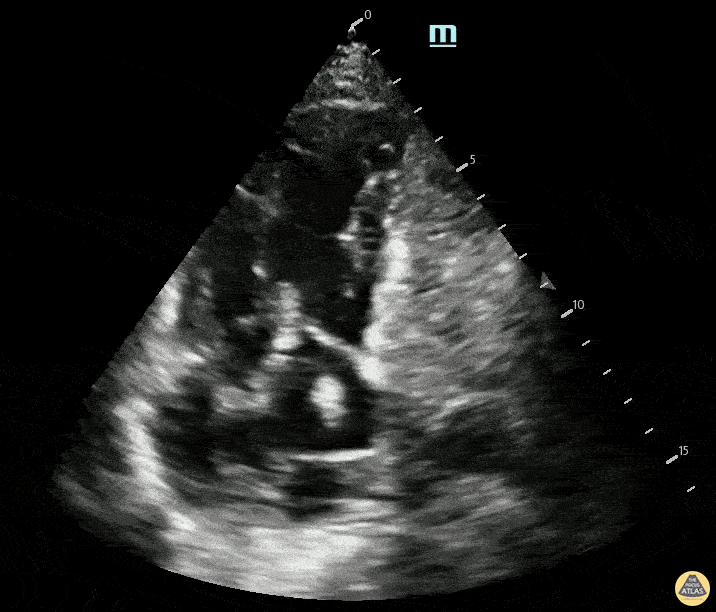

Right Ventricular Dysfunction - Apical 4 Chamber view demonstrating massive PE with RV dilation, D-sign, and McConnel sign with clot in transit

An elderly female presented with 3 days of shortness of breath. Apical 4 chamber view identified clot in transit, severe RV dilation, and McConnell’s sign on bedside ultrasound prior to CT confirming saddle PE Contributed by: Max Goder-Reiser, MD